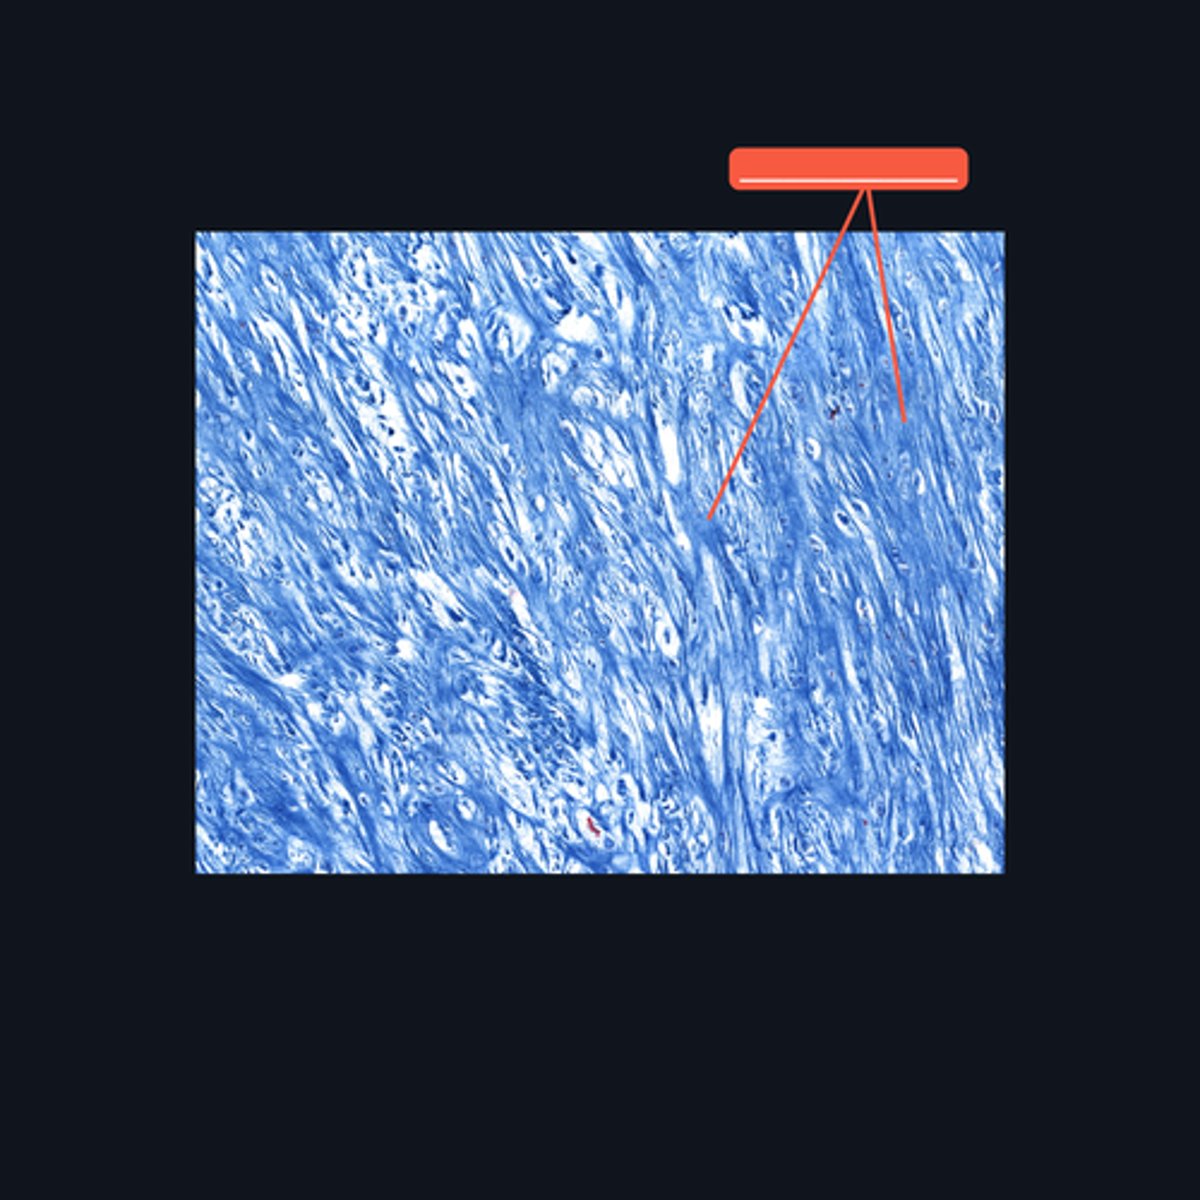

Fibrocartilage; intervertebral disc, articular disc, glenoid and acetabular labra

What type of cartilage is in the image? Where is this specific type of cartilage found?

Collagen fibers

This type of cartilage is abundant in what fibers?

Dense regular connective tissue; chondrocytes; lacunae

This cartilage is commonly mistaken as _____. However, when examined closely, _____are contained in _____ (identify pointed structures), making it a cartilage.